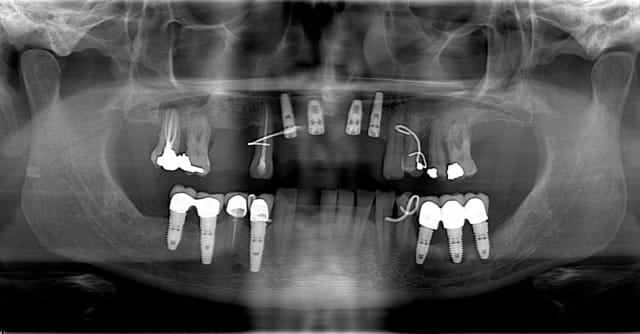

un an après !

ça s'arrange pas, voyez plutôt..

augmentation de la perte osseuse +++

7 les radios post-op